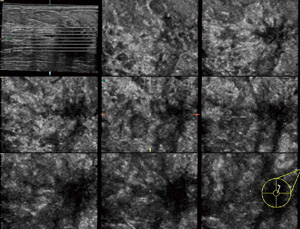

●Volume Imagingで客観性を向上

3Dプローブを用いて,疾患を立体的にとらえます。通常のプローブでは得られないC断面や任意断面の情報が,検査者に依存せず容易に得られます。CTやMRIと同様な複数断面表示による画像解析も行え,腫瘤や乳管の広がり,乳がんによる周囲組織引き攣れなどが確認できます。

3DプローブによるTUI表示